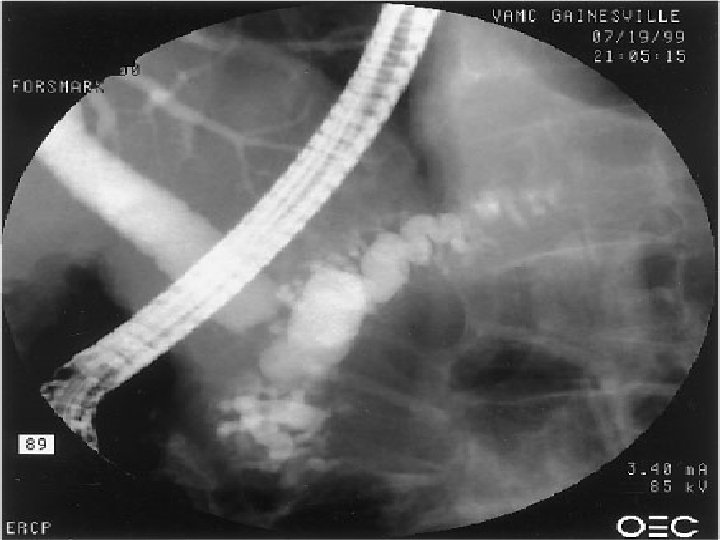

Pankreas kanalında taş